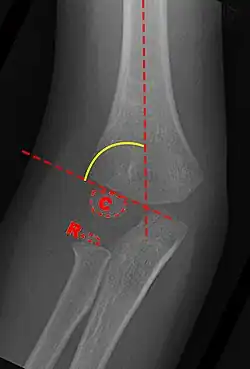

Anterior X-ray

Carrying angle can be evaluated through AP view of the elbow by looking at the Baumann's angle.[3] There are two definitions of Bowmann's angle:

The first definition of Baumann's angle is an angle between a line parallel to the longitudinal axis of the humeral shaft and a line drawn along the lateral epicondyle.

Another definition of Baumann's angle is also known as the humeral-capitellar angle. It is the angle between the line perpendicular to the long axis of the humerus and the growth plate of the lateral condyle. Reported normal values for Baumann's angle range between 9 and 26°.[7] An angle of more than 10° is regarded as acceptable.[7]